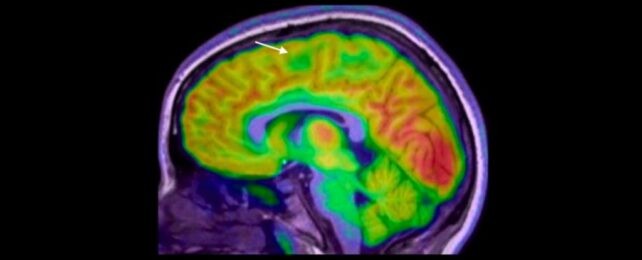

Во студијата, 80% од децата со кортикална дисплазија и фокална епилепсија веќе имале МРИ што била оценета како „нормална“. Со помош на вештачката интелигенција – преку анализа на МРИ и ПЕТ снимки – алатката успеала да детектира лезии со точност од 94% кај една група и 91% кај друга. Од 17 деца во првата група, 12 биле оперирани, а 11 од нив веќе немаат напади. Следната цел е тестирање на алатката во реални болнички услови кај нови пациенти.